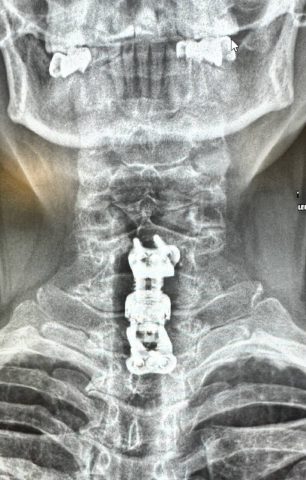

Хирургам было необходимо устранить компрессию спинного мозга, а также удалить тела поражённых позвонков и зафиксировать позвоночник. Когда это было сделано, врачи приступили к установке телоскопического телозамещающего импланта.

Операция прошла успешно и помогла женщине забыть об онемении и боли в руках.